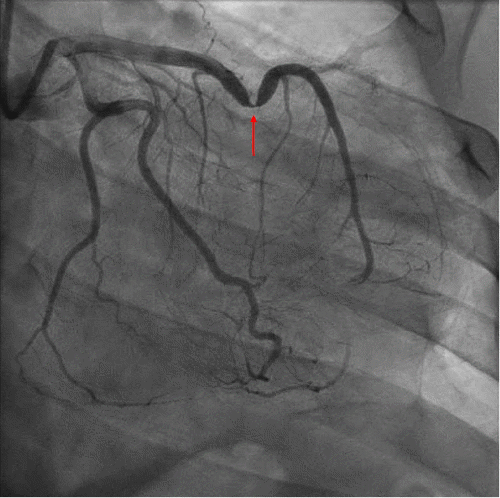

Post-procedure, the patient exhibited persistently elevated troponin levels and ST elevations on electrocardiogram (ECG). Echocardiography revealed severely reduced left ventricular function (ejection fraction 25-30%). Cardiac MRI confirmed a recent large LAD territory infarct with myocardial edema and microvascular obstruction. Post-PCI CT angiography showed severe mid-LAD stent compression and stenosis, along with bulging of the left ventricle and hypodense myocardium, consistent with acute myocardial infarction (Figure 2).

Figure 2. Coronal CT Angiogram Depicting Left Ventricle with Areas of Impingement by Pericardium (arrows). Published with Permission